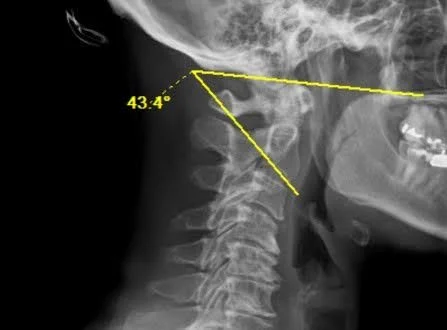

The Occiput C2 angle (OC2 angle) measures the angular relationship between the occiput and the axis (C2 vertebra) on a lateral cervical spine radiograph. It is the primary radiographic parameter used to quantify craniocervical sagittal alignment and is critical for preoperative planning and intraoperative assessment during occipitocervical fusion (OCF).

The OC2 angle is defined as the angle between McGregor’s line (a line connecting the posterior edge of the hard palate to the most caudal point on the midline occipital curve) and a line drawn along the inferior endplate of C2. This measurement reflects the degree of flexion or extension at the craniocervical junction.

•   Measure the angle formed between McGregor’s line and the inferior endplate line of C2

•   A larger (more positive) angle indicates relative extension at the craniocervical junction; a smaller (decreasing) angle indicates relative flexion